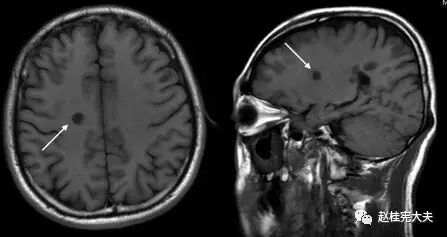

图3. 示双侧额顶叶皮层及皮层下、深部白质内多发长T1信号病灶,称“黑洞”(black hole)。

图8. T2FLAIR像示(左图)上箭头—皮层病灶;(左图)下箭头、(右图)皮层下病灶。

图9. T2 FLAIR像示(右图)皮层下累及U形纤维病灶。

图10. (上图)T1、(下图)T2 FLAIR像示:病灶累及脑桥、延髓、双侧小脑。